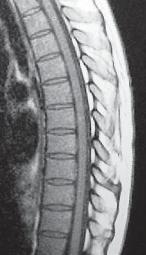

МРТ № 51

Иллюстрация к книге — Остеохондроз для профессионального пациента [i_084.jpg]

На МРТ № 51 наблюдается грудной отдел позвоночника с нормально выраженным физиологическим кифозом, межпозвонковыми дисками и спинным мозгом.

Рассмотрим вариант нормы и патологии грудного отдела позвоночника (МРТ № 51, МРТ № 52). Конечно, заболеваний, которые могут проявиться вследствие развития остеохондроза грудного отдела позвоночника, достаточно. В каждом отдельном случае необходимо установить точный диагноз, осуществить грамотный подход в выборе методов лечения. Нельзя недооценивать возможные вариации развития заболевания. Вот, например, из-за таких деформаций позвоночника, которые можно наблюдать на МРТ № 52, порой возникают парезы или параличи, зачастую вследствие развивающегося ишемического «миелита», точнее спондилогенной миелопатии — перерождение вещества спинного мозга из-за недостаточного кровоснабжения. Причём то же клиническое течение спондилогенной миелопатии может протекать двояко. Чаще заболевание развивается исподволь, постепенно в течение довольно длительного времени. Порой останавливается, так и не достигнув своего апогея. А бывает (хотя и намного реже) в течение относительно короткого отрезка времени, на фоне полноценной функции спинного мозга, возникают парезы и параличи. Что лежит в основе этого тяжелейшего осложнения — спондилогенной миелопатии? Как правило, расстройство кровоснабжения спинного мозга. Оно, в свою очередь, возникает вследствие нарушения проходимости питающих его артериальных кровеносных сосудов. Опасность здесь таится в том, что значительный по длине спинной мозг, занимающий почти всю протяжённость позвоночника, получает кровоснабжение всего из нескольких артерий. Если даже одна из таких питающих артерий вследствие перерастяжения или сдавления «закупоривается», то значительные территории спинного мозга лишаются кислорода, питательных и других веществ, что приносит с собой его тканям артериальная кровь. Нарушение проходимости питающих спинной мозг кровеносных сосудов возникает вследствие их перерастяжения вместе со спинным мозгом и его элементами, что или приводит к сужению просвета растянутого артериального ствола или к прямому сдавлению его деформированными костными структурами позвоночника. Нервная ткань спинного мозга очень чуткая к недостаточности кровоснабжения и быстро гибнет в условиях неполноценного притока артериальной крови. Это, в свою очередь, приводит к возникновению частичных и полных параличей тех органов, которые зависят от поражённых территорий спинного мозга. Вот такая выстраивается цепочка, где одно событие неумолимо порождает другое и приводит к определённым последствиям.